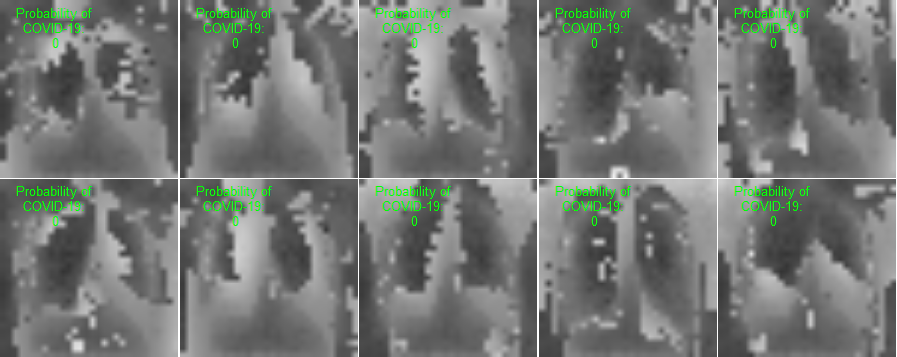

This section presents visualization of the proposed architecture. These visualizations are presented in Figure 5. Unlike Figure 2 that is an executive summary with each position representing many samples, these visualizations in Figure 5 are sample-wise plots. In other words, the 10 original images that are sized 128 by 128 in Panel A and Panel B are the same samples in the second row, 1st Conv. Layer, and the third row, 2nd Conv. Layer.

Visualization Interpretation The plot in Figure 5 of the original images for COVID-19 patients has grey and cloudy textures in chest area. Because an X-ray picture is at its brightest when most of the light beams emitted are bounced back from the object, we can observe bones to be the color “white” while the margin to be completely “black”. For muscle and organs inside human body, X-ray beams that are emitted can only partially be collected and this causes the greyscale on the X-ray images in chest area. For COVID-19 patients, there are grey and shaded area in the chest X-ray pictures. This is due to the inflammatory fluid when patients exhibit pneumonia-like symptoms. The fluid inside chest area is a consequence of human immune system fighting against outside diseases. This shaded (as seen in Panel A of Figure 5) prevents us from observing the clear location of lungs. This is different in Panel B where the lung areas are dark and almost black, because a healthy lung is filled with air (i.e. normal cases and X-ray image presents color black). The black and white contrast in the two panels is directly related to how much inflammatory fluid there is in human lungs. This contrast translates to greyscale on pictures and it is directly related with COVID cases and non-COVID cases (i.e. response variable ). The same contrast can be seen using the new variables (these are ’s based on equation 4) in the 1st Conv. Layer (sized 61 by 61). For COVID-19 patients, the lung area is cloudy and unclear while the healthy cases it is clearly visible. This is not a surprising coincidence because the proposed new variable modules, ’s, are engineered using equation 4 which relies on the response variable in training set. The images sized 61 by 61 from the proposed algorithm is a direct translation of not only the original pixels but also response variable. In other words, this visualization presents how I-score sees image data.

| 2nd Conv. Layer: 30 by 30 | 2nd Conv. Layer: 30 by 30 | |

| (Starting Point = 6, Window 2 by 2, Stride = 2) | (Starting Point = 6, Window 2 by 2, Stride = 2) | |

| Remark: variables | variables | |

| Same 10 images above with 900 variables | Same 10 images above with 900 variables | |

| Labels predicted using Model 4 | Labels predicted using Model 4 | |

| Row (c) |  |

This figure presents visualization summary for 10 randomly sampled images from COVID class and non-COVID class (each has 10). Panel A is for COVID patients and Panel B is non-COVID people. The first row plots the original images that are sized 128 by 128. The 1st Conv. Layer generates new variables. We plot the same 10 images from both classes using these 3,721 variables in the second row. We also print the predicted COVID probabilities on top left corner of each image. The 2nd Conv. Layer generate variables. We plot the same 10 image samples from both classes using these 900 variables in the third row. We also print the predicted COVID probabilities on top left corner of each image assuming using only these 900 variables as predictors. The plot of the original images for COVID-19 patients has grey and cloudy textures in chest area. This is due to inflammatory fluid when patients exhibit pneumonia-like symptoms. This shaded (as seen in Panel A) prevents us from observing the clear location of lungs. This is different in Panel B where the lung areas are dark and almost black which means the lung is filled with air (i.e. normal cases). The black white contrast in the two panels is directly related to how much inflammatory fluid there is in human lungs which translate to greyscale on pictures. The same contrast can be seen using the new variables (these are ’s based on equation 4) in the 1st Conv. Layer (sized 61 by 61). For COVID-19 patients, the lung area is cloudy and unclear while the healthy cases it is clearly visible.

1st Conv. Layer. to 2nd Conv. Layer. From the resulting matrix of the 1st Conv. Layer, we are left with 3,721 variables. We go through the proposed design in Table 4 and we create a new convolutional layer, i.e. 2nd Conv. Layer. This new layer has variables. We take the same 10 sampled images from before and we use these 900 variables to present these images. In this presentation, we resize these 900 variables into shape 30 by 30. In other words, we get a smaller matrix that we can plot that exhibit mini version of similar patterns as before. We use Model 4 to generated the predicted probabilities. These probabilities are printed on the top left corner of each image and they are color coded similarly as before (red probabilities have ground truth of COVID class while green probabilities have ground truth of non-COVID class).